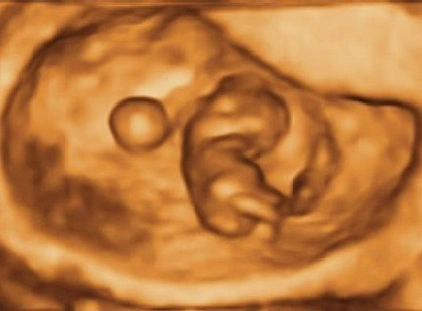

Dating Scan

Your Doctor may request this scan if you are unsure about your dates, you have bleeding or pain or if your doctor suspects a multiple pregnancy. The scan may also be performed if there is a history of ectopic pregnancies or recurrent miscarriage. Due to the small size of the baby at this early stage a transvaginal scan is normally performed. A transabdominal probe may also be used.

This scan will provide you with the following information:

1. The number of embryos and the pregnancy location. This can rule out an ectopic pregnancy.

2. The baby's heat rate. (This is usually present by 6 weeks)

3. The size of the embryo which will help to determine pregnancy dates. This is accurate to ± 3 days between 7 and 11 weeks. After 11 weeks the accuracy drops to ± 7 days because the baby curls up into the fetal position. We will also check for the presence of uterine fibroids or ovarian cysts.

The images provided by this scan are quite varied because the baby is growing so rapidly.

Less than 5 weeks: pregnancy is unlikely to be detected by scanning

5 – 6 weeks: A small gestation sac is seen

6 – 8 weeks: A small embryo around 5 mm is seen at 6 weeks

9 – 10 weeks: Limbs begin to develop

11 – 12 weeks: Baby curls up into fetal position

Dating scans may be done after 12 weeks if the nuchal has not been done and it is too early for a morphology scan